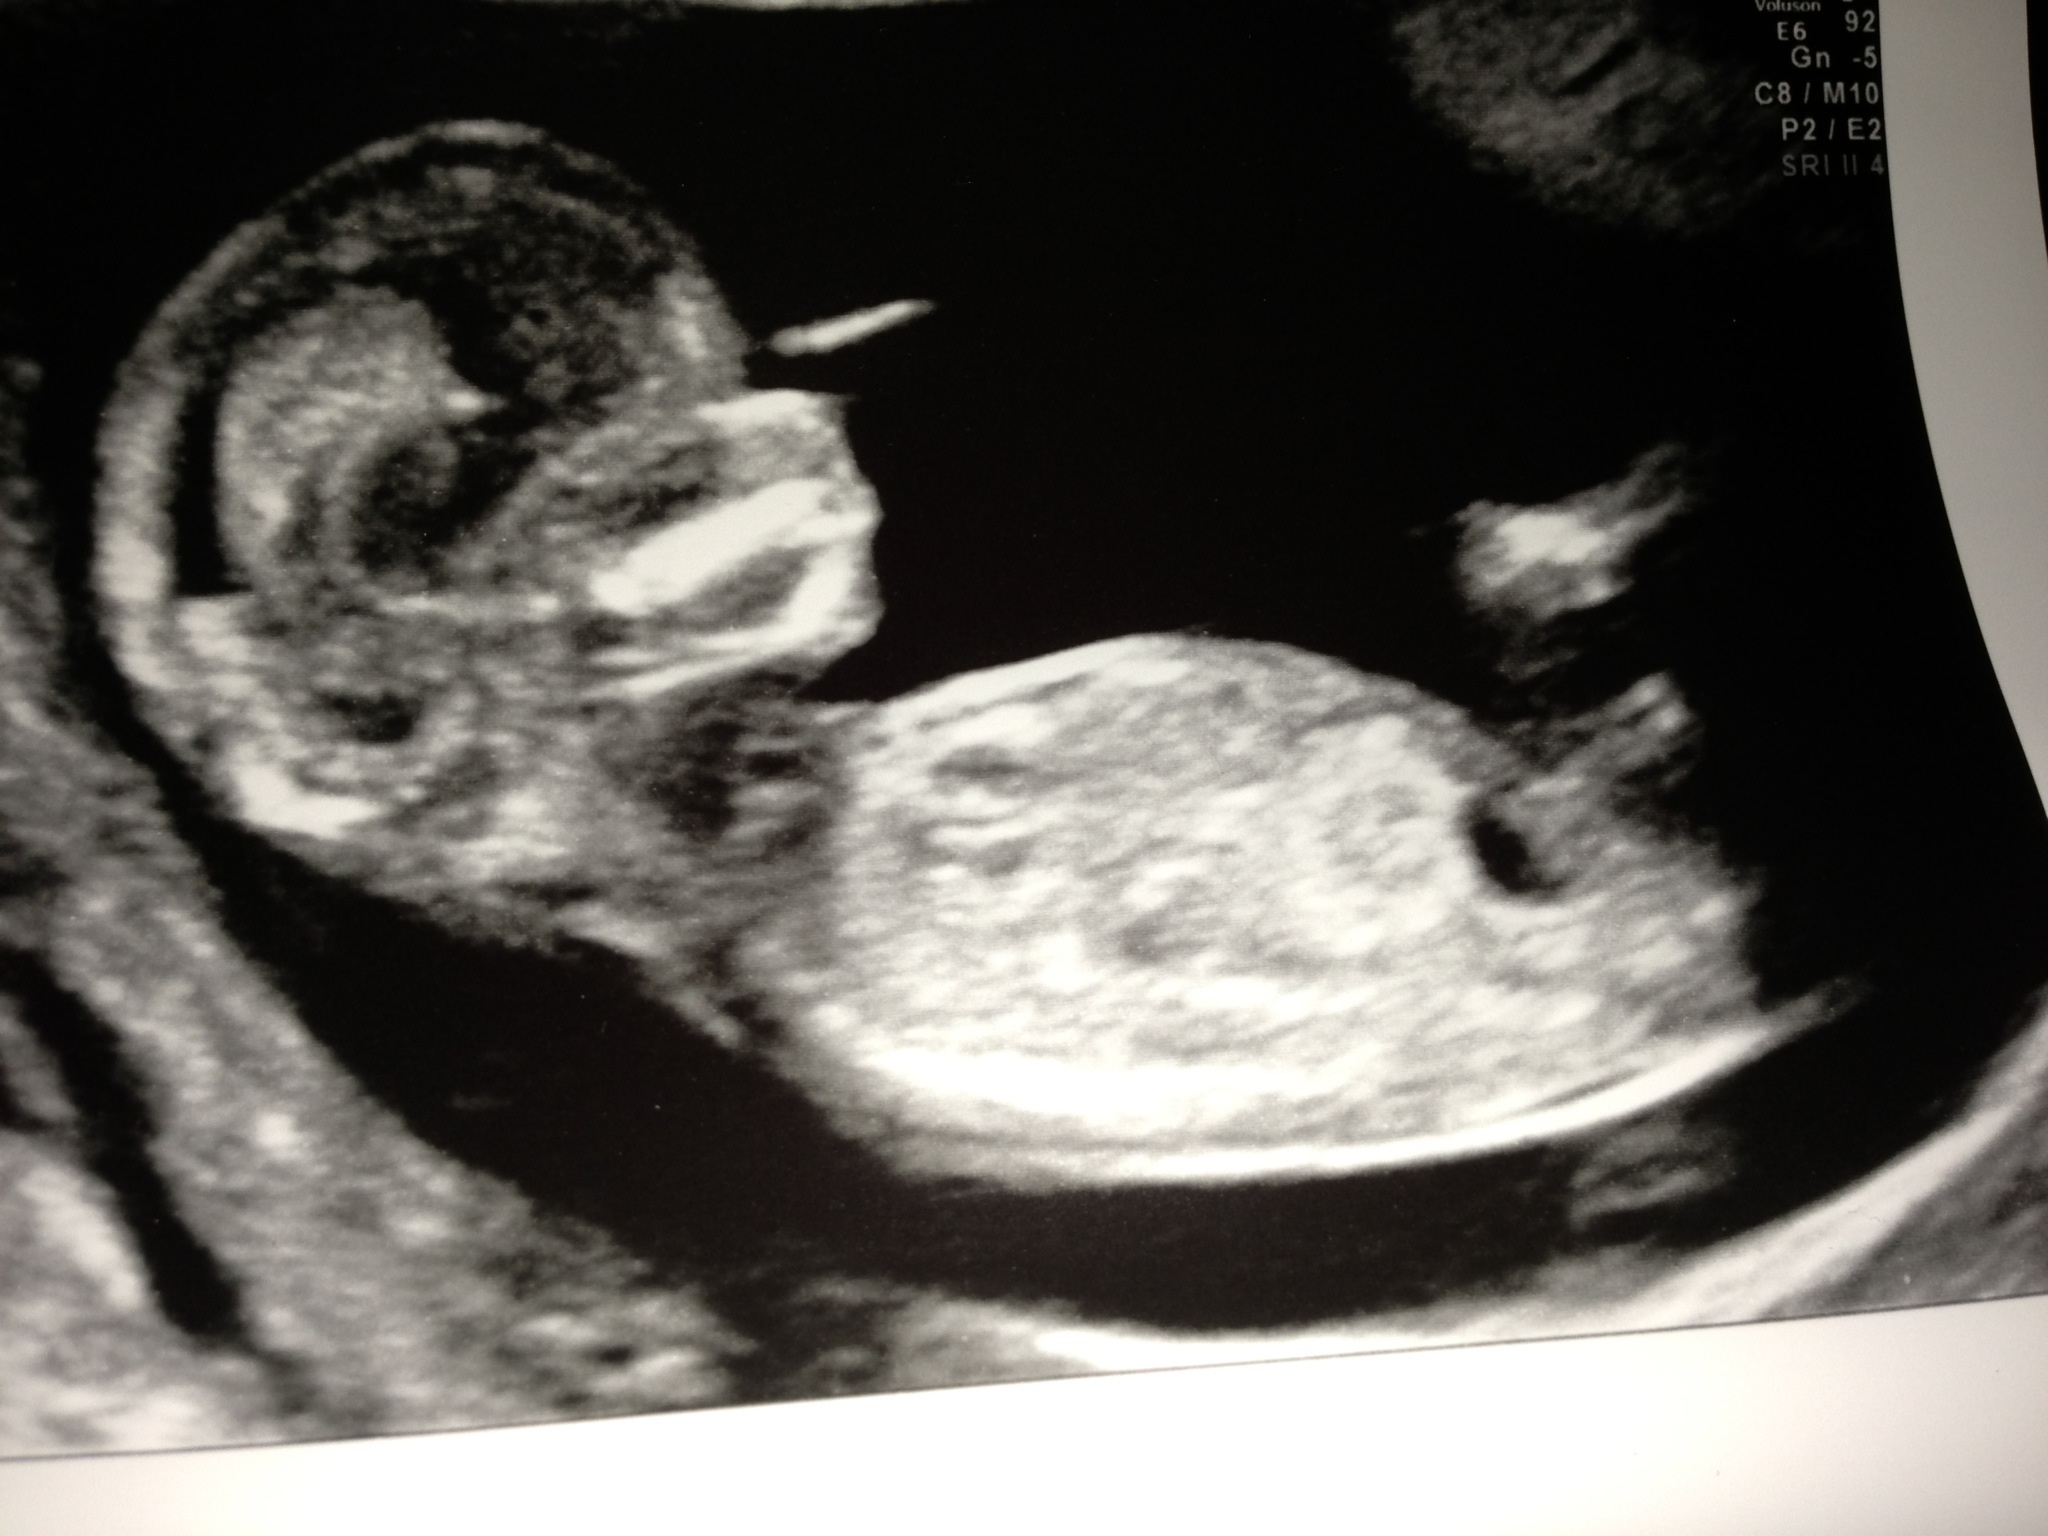

Hi I posted my us pics and have studied my previous children's pics and the nub on theirs looks defined which makes me think this is not a nub - can anyone explain what it is though in the nub area? Sorry to be a pain but struggling a bit at mo. thanks for looking and helping ...

Attachment 7289Attachment 7290